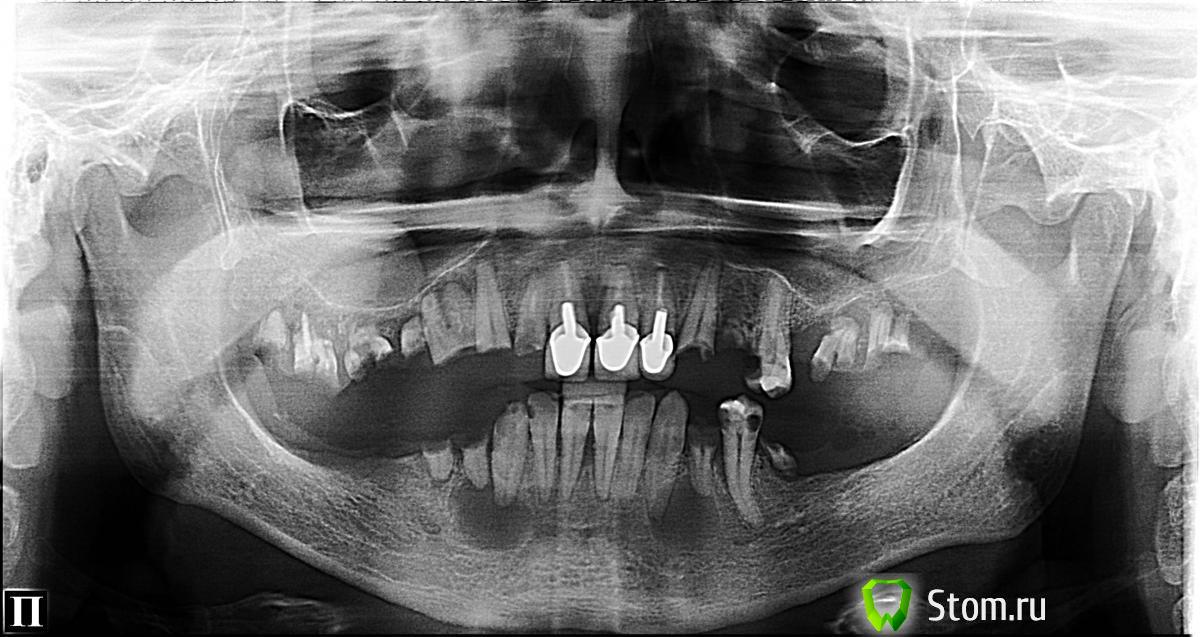

FBR Опубликовано 22 марта, 2012 Поделиться Опубликовано 22 марта, 2012 (изменено) Будет вот так. Изменено 22 марта, 2012 пользователем FBR 1 Ссылка на комментарий